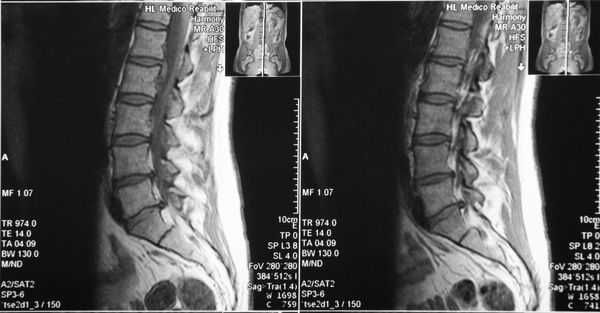

(Слева) Т2-ВИ, сагиттальный срез: массивная оссификация ЗПС, вызывающая тяжелую компрессию грудного отдела спинного мозга. Обратите внимание на сочетанную оссификацию желтой связки.

(Справа) Т1-ВИ, сагиттальный срез, пациент с непрерывной формой ОЗПС грудного отдела позвоночника спереди от спинного мозга: низкоинтенсивное объемное образование, вызывающее тяжелую компрессию спинного мозга. У пациента отмечается клиника тяжелой миелопатии. Обратите внимание на признаки оссификации и желтой связки.д) Клинические особенности: